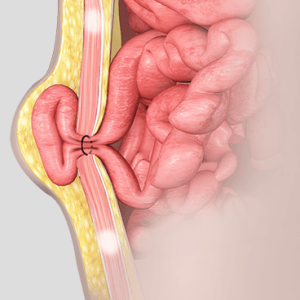

جراحـة الفـتـق

جراحة الفتق هي إجراء طبي يتم إجراؤه لإصلاح الفتق، الذي يحدث عندما يبرز عضو أو نسيج من خلال نقطة ضعف في العضلات أو الأنسجة الضامة المحيطة.